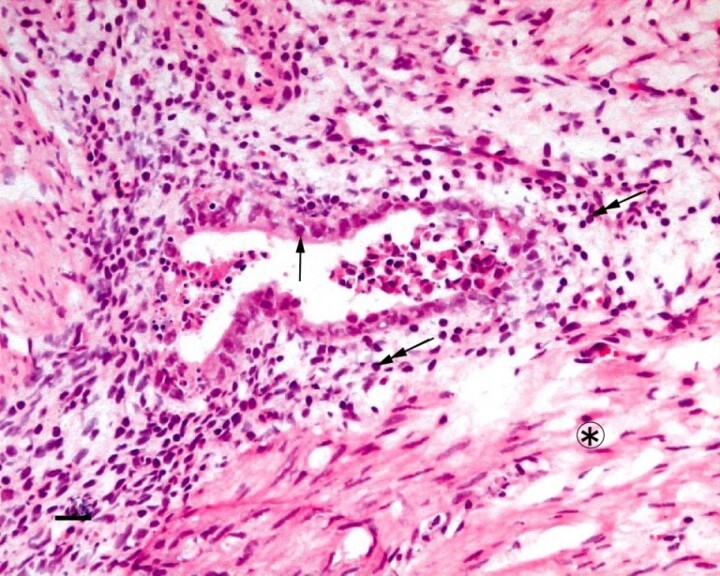

1.病巣治癒の実績①H・E染色

<EMP9注入前後でのH・E染色の変化>

矢印:腺上皮/二重矢印:間質細胞/*印:平滑筋線維

無処理

EMP9注入後